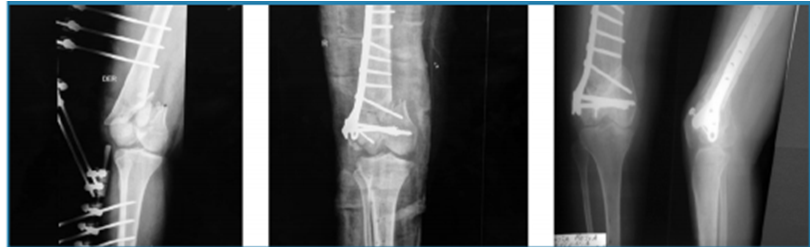

· 3 pacientes con fracturas de meseta tibial, en las cuales se realizó osteosíntesis con placa bloqueada más aloinjerto de 30 cc.

· 3 pacientes con fracturas de tercio distal de fémur supraintercondíleas con gran defecto óseo, para las cuales se utilizó placa condilar bloqueada en todas, se usó en un paciente 30 cc de aloinjerto de chip de esponjosa y en 2 aloinjerto de 60 cc de chip esponjosa (Fig. 2 y 3).

· 5 pacientes con pseudoartrosis, 3 correspondientes a meseta tibial a quienes se realizó osteosíntesis con placa de soporte en L y aloinjerto de chip de esponjosa 50 cc, 2 de fémur distal resueltas con placa condilar bloqueada con 60 cc de chip esponjosa y un paciente con fatiga de material de osteosíntesis (Fig. 4 y 5).

Las fracturas de meseta tibial, calcáneo y fémur distal presentaron una media de hospitalización de 12 días, se logró la consolidación en 90%, el tiempo promedio fue de 8 meses (4 -9 meses). En uno de los casos se realizó una reintervención quirúrgica por mala técnica.